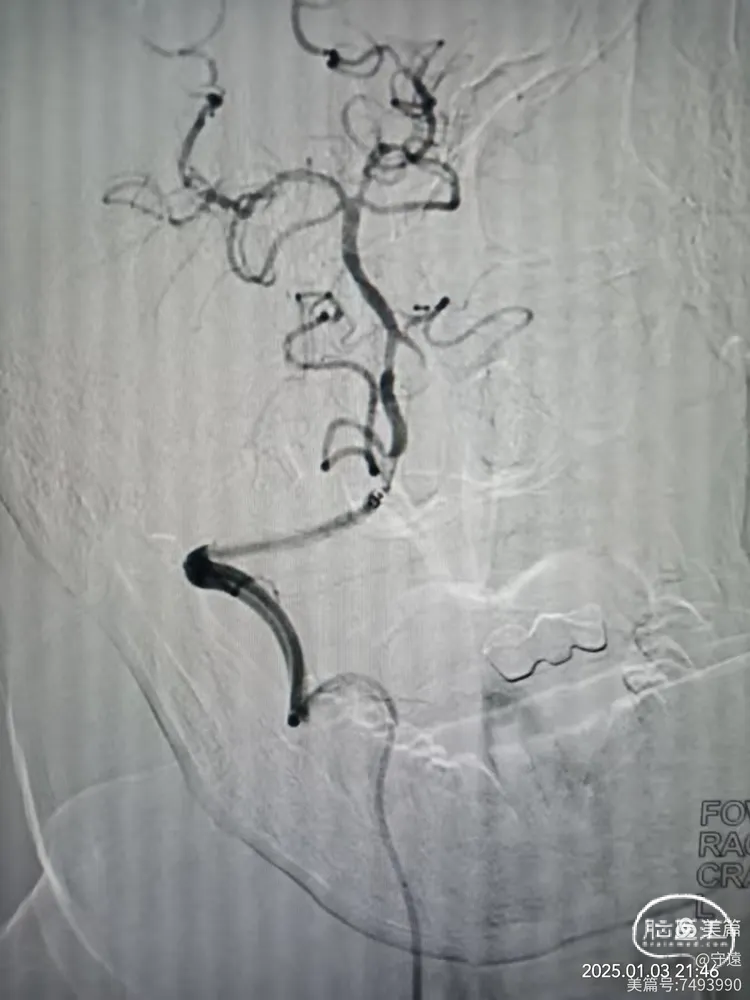

经桡动脉造影:左侧椎动脉起始终部中度狭窄。向颅内供血缓慢,v4段闭塞。

右侧椎动脉为优势椎,血流迟滞,V2以远未显影,考虑V4 闭塞。

右侧椎动脉顺应,更换6F动脉鞘经桡动脉入路行基底动脉开通。

泥鳅导丝导引6FGT68血栓抽吸导管,泥鳅导丝不出头,内芯支持抽吸导管到达V3段。

踹马桶抽吸出小块硬质血栓。

微导管造影显示Ⅴ4狭窄。

微导丝携带2.5*15mm球囊在V4~基底动脉下段扩张。

撤出球囊血管,造影显示再次闭塞,考虑夹层或回弹可能。

球囊穿梭:跟进抽吸导管至狭窄部位,再次输送球囊至狭窄部位。球囊半含状态下再次在7个大气压下扩张。

撤出球囊,踹马桶抽吸出暗红色血栓。

微造影显示:血管再通

回撤导管至V3段造影,狭窄不明显,血流通畅。

回撤至椎动脉起始段造影血流通畅,左侧大脑后似有少量血栓逃逸,推注替罗非班10mL,结束手术。